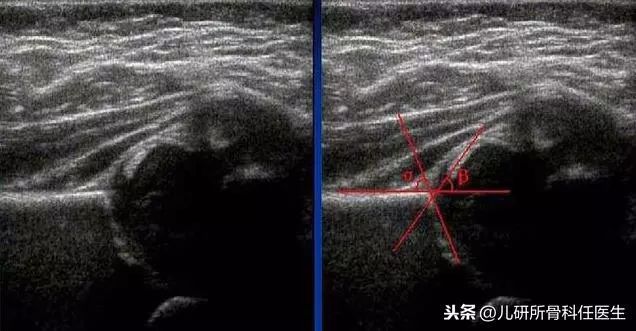

这是许多家长做完超声的苦恼,对于非专业的医生也很难看懂超声结果。当前国际通用的髋关节检查方法为Graf法髋关节超声检查,通过确立的髋关节的测量值,可以做形态学评估检查。

检查结果以Graf分型,共分为四型,只有I型是属于正常的髋关节,其他分型都需要及时治疗。具体的治疗方法在此暂不展开讨论,发现问题,建议直接找专业医生获得治疗意见。